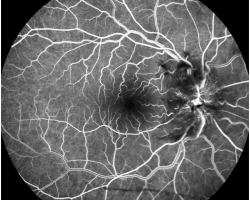

- Angiographie fluorescéine : papillite à droite, normal à gauche

- Angiographie fluorescéinique, OCT et périmétrie cinétique (cf. supra). Pour information : pas de déficit de l’OCT RNFL à gauche (non interprétable à droite du fait de l’œdème papillaire). Pas de déficit de la couche des cellules ganglionnaires à gauche (liée probablement à une poussée de névrite gauche ancienne ou présence de lésion démyélinisante en rétrochiasmatique vu la congruence du déficit du champ visuel des deux yeux).